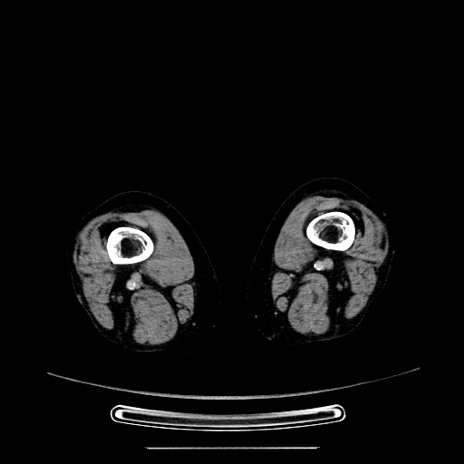

【症例】70歳代女性

【主訴】お腹が張る

【現病歴】1週間くらい前から腹部膨満の自覚あり。昨日夜から増悪したため、本日救急外来受診。

【身体所見】意識清明、BT 36.5℃、BP 165/106mmHg、HR 80bpm、SpO2 98%、腹部:膨満、軟、自発痛・圧痛なし、触診にて不快感あり、腸蠕動音:減弱

【データ】WBC 12600、CRP 1.04